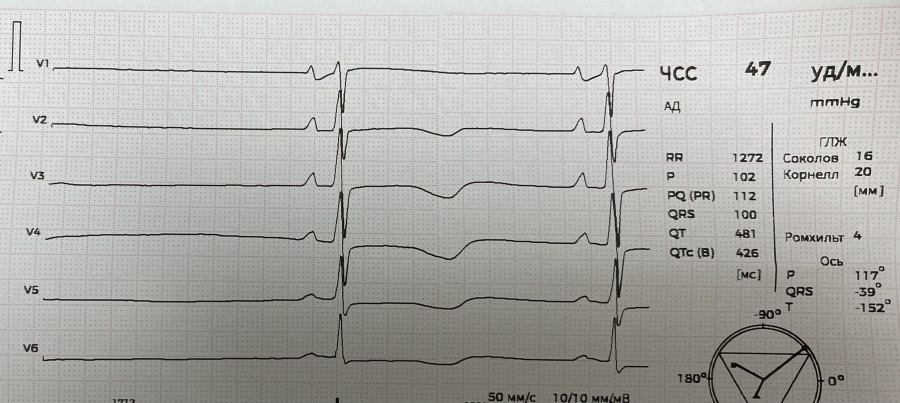

М 37. Перикардит эксудативный на фоне ушиба сердца. ЭКГ до дренажа.